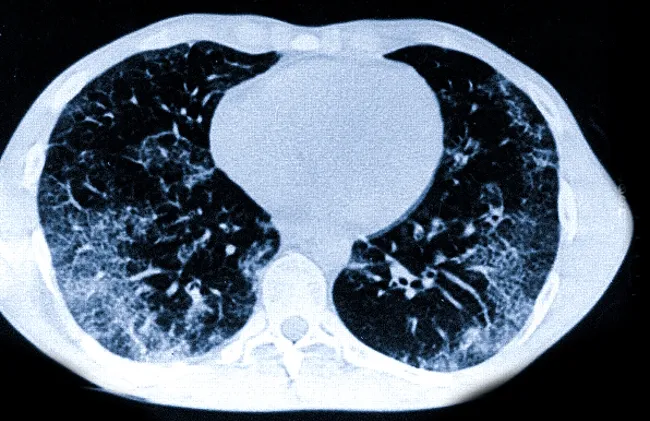

Комп’ютерна томографія легень — один із найточніших методів оцінки стану легеневої тканини. Саме КТ дозволяє виявити зміни, які часто не видно на звичайній рентгенографії. Однак для пацієнтів висновок радіолога може виглядати складним і незрозумілим: у ньому зустрічаються такі терміни, як «матове скло», «консолідація», «ретикуляція» або «фіброзні зміни».

Термін «матове скло» (ground-glass opacity) означає ділянку легеневої тканини з підвищеною щільністю, через яку все ще видно судини та бронхи.

Головна особливість «матового скла» — часткове збереження повітряності легені. Саме тому на КТ просвічуються судини.

Ретикуляція — це поява на КТ дрібної сітчастої структури в легенях. Вона формується через потовщення міжальвеолярних перегородок або сполучнотканинних елементів.

На зображенні це виглядає як тонка сітка або мережа.

Ретикуляція часто поєднується з іншими ознаками — наприклад, «матовим склом».

У висновку КТ можна зустріти фразу «дифузні зміни». Це означає, що патологічний процес поширюється не на одну локальну ділянку, а охоплює значну частину легеневої тканини або обидві легені.

Отже, КТ легень дає детальну інформацію про структуру легеневої тканини. Терміни «матове скло», «консолідація», «ретикуляція» або «фіброз» описують різні типи змін, які можуть виникати при запальних, інфекційних або хронічних процесах.